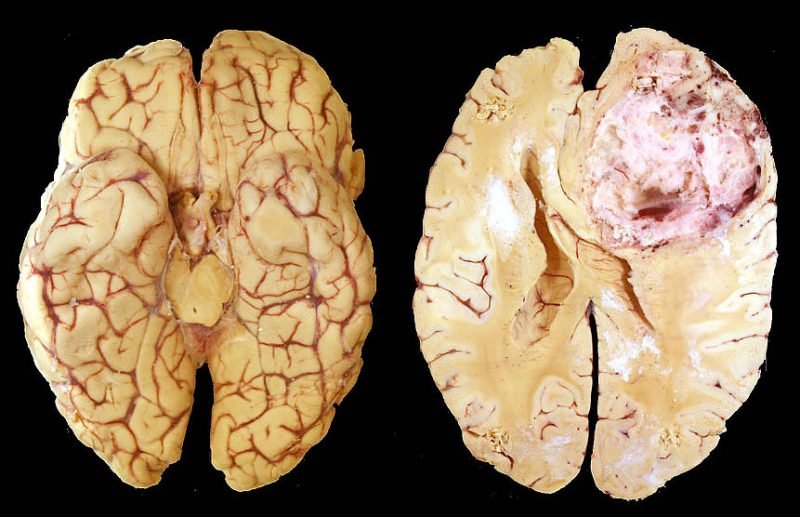

Онкопроцесс, формирующийся из соединительнотканных элементов и локализующийся внутри черепной коробки — это саркома головного мозга. Как правило, представляет собой узловое новообразование, обладающее способностью прорастать в соседние структуры. Оно отличается быстрыми темпами роста и ранним метастазированием. Поэтому прогноз в большинстве случаев неблагоприятный.

По локализации принято рассматривать саркомы внутримозговые – в виде плотного узла с нечеткими границами и элементами обызвествления, а также внемозговые – с четкой капсулой и способностью быстро вовлекать в процесс соседние ткани.